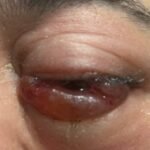

Orbital compartment syndrome (OCS) is an ophthalmologic emergency due to an acute rise in intra-orbital pressure and can result in permanent vision loss, oftentimes requiring emergent surgical decompression. Orbital compartment syndrome most commonly occurs due to recent trauma and is often easily diagnosed by history and physical exam. However, there are other causes of OCS where a more subacute/chronic rise in pressure can lead to an atypical presentation. This is a case report of a 48-year-old male who presented with left eye pain and swelling for the past 6 months. The patient had seen two ophthalmologists prior to his emergency department (ED) presentation who had prescribed him an antibiotic ointment, oral steroids, and steroid eye drops. The physical exam in the ED was concerning for increased intra-ocular pressure (IOP) and decreased vision. Ophthalmology was consulted and requested magnetic resonance angiography (MRA) to assess a vascular etiology given tortuous retinal vasculature. Emergent surgical decompression was deferred due to chronicity of symptoms, and patient was started on dorzolamide/timolol and brimonidine eye drops as well as intravenous (IV) acetazolamide with subsequent improvement in IOP. Imaging revealed a left carotid-cavernous sinus fistula (CCF), and the patient was admitted to neurosurgery. Patient successfully had an embolization with subsequent normalization of IOP and improvement of symptoms. This case is a good example of how non-traumatic causes of OCS can lead to misdiagnosis and how surgical decompression could potentially be deferred in subacute OCS.